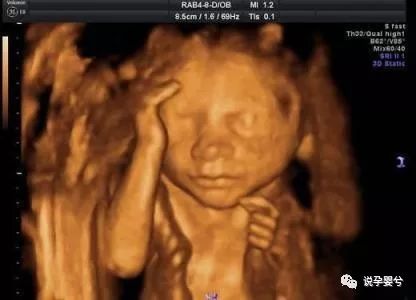

1、B超不能判断所有问题

根据目前的医疗水平,B超主要是检查胎儿是否存在一些结构上和缺陷,比如脑积水、脊柱裂、先天的单腔心和无脑等。但是产检并没有跟对所有问题都做出准确的判断。

2、超声检查可能也有漏洞

超声检查也是目前产前诊断的主要途径。但是,超声波检查也是有局限性的,受到被检孕妇腹壁情况、胎儿体位等具体情况影响,也可能存在漏诊或误诊。